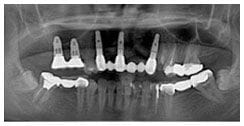

X 光片

術後X光片